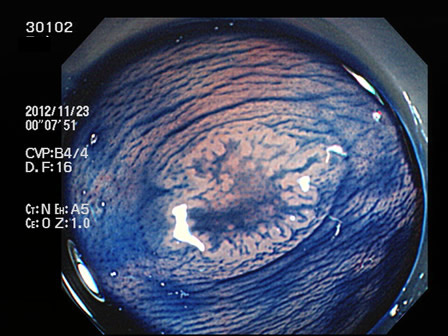

上記100名より抽出した平坦・陥凹型腺腫(=癌化の危険が高いが見落としやすい病変)の内視鏡写真